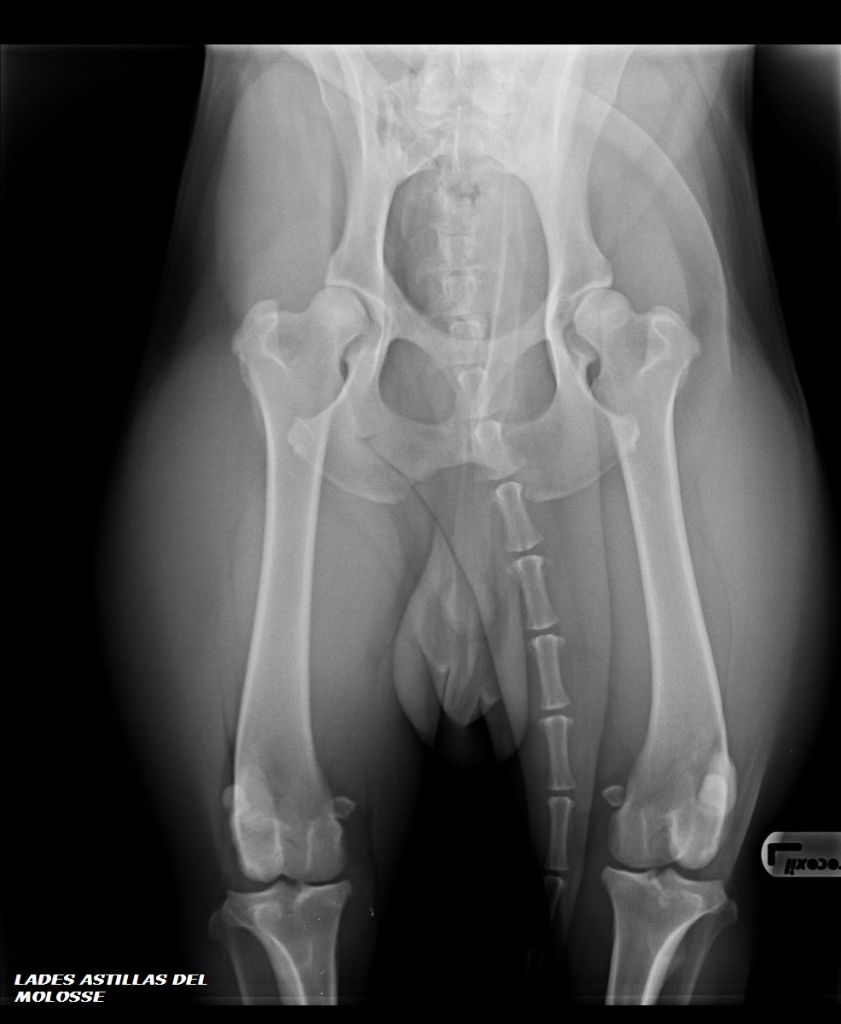

Ladès Astillas Del Molosse

Dogue de Majorque

radio des hanches

3 ans